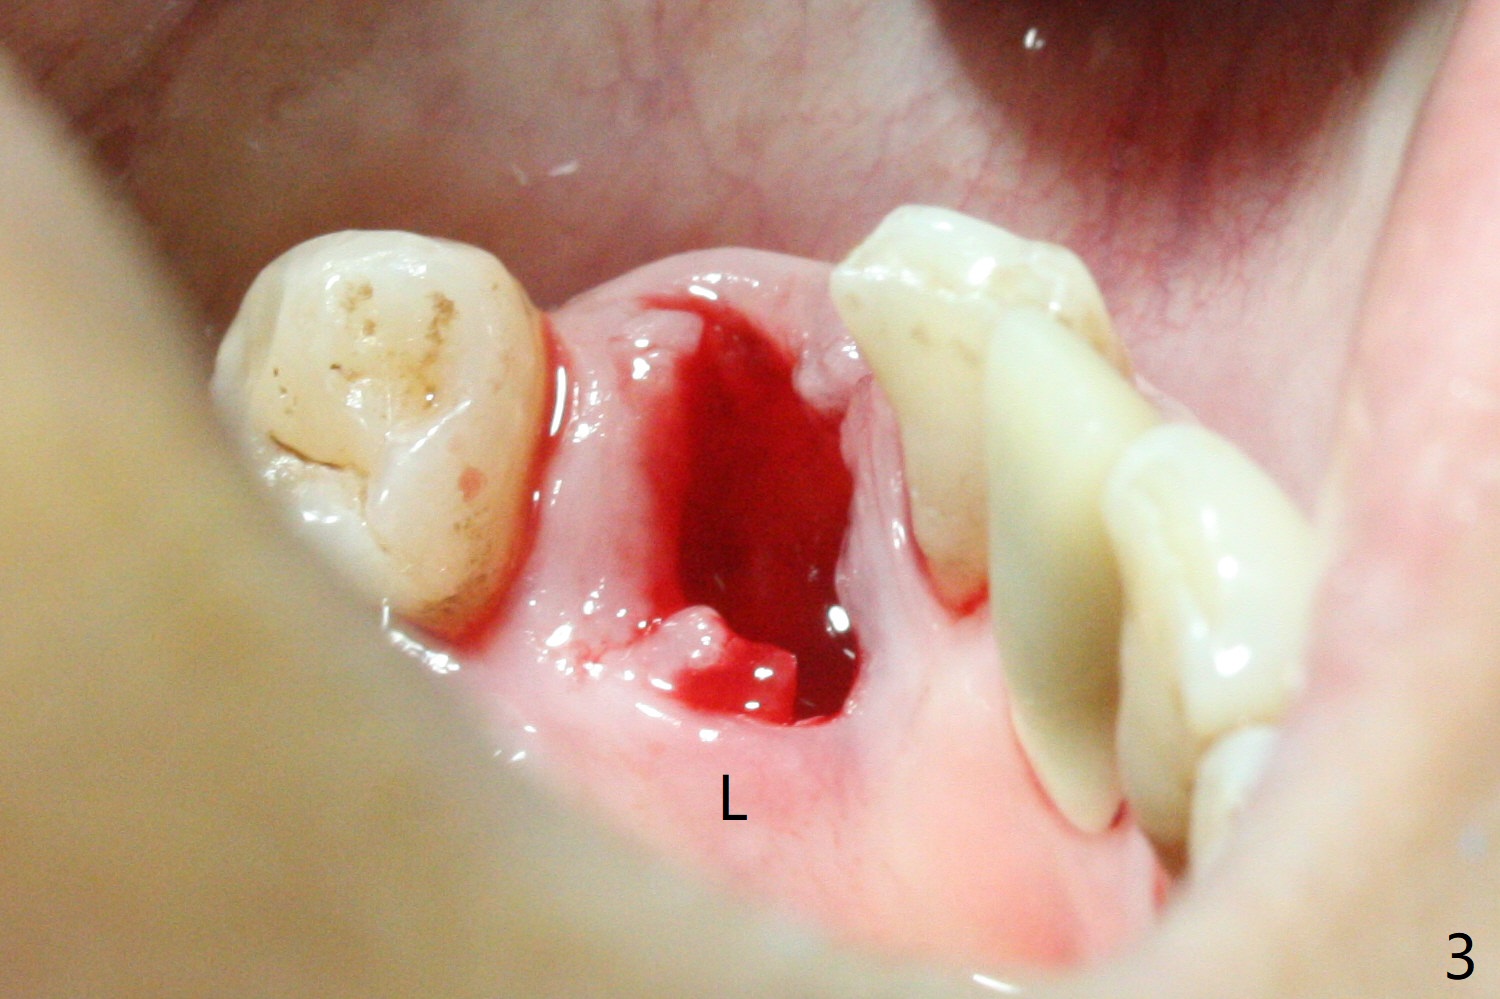

There is a fistula buccal to the apex of the tooth #23 preoperatively (Fig.1), which is related to loss of the buccal plate of the socket of #23. Therefore an implant is placed mainly in the socket of #22 (Fig.3). The lingual (Fig.2 L) gingiva appears to have more extensive inflammation. After extraction, the lingual (Fig.3 L) gingival margin is significantly lower than the buccal one. The lingual crest is ~ 4 mm lower than the buccal one. A 3.8x10 mm dummy implant is placed tentatively with an apical space (Fig.4). When a same dimension definitive implant is placed with 40 Ncm, it is 2 mm below the lingual gingival margin, whereas 6-7 mm below the buccal one (Fig.5). Vanilla graft is placed before placement of a 5.5x4(5) mm abutment (Fig.6,7). There is a 2-3 mm lingual (L) gap to be filled with the allograft secondarily to prevent periimplantitis (Fig.7). Later the abutment is changed to a longer and smaller one (Fig.8) with more of the allograft (*). After trimming of the abutment (Fig.9 (*: papilla between the fused teeth)), an immediate provisional is fabricated to close the socket (Fig.10, similar to Fig.1). The majority of the bone graft seems to be in place 8 months postop (Fig.12). The implant appears to have been placed buccal, consistent with the thin and slightly erythematous buccal gingiva (Fig.13). The ridge completely regenerates 2 years post cementation (Fig.14).